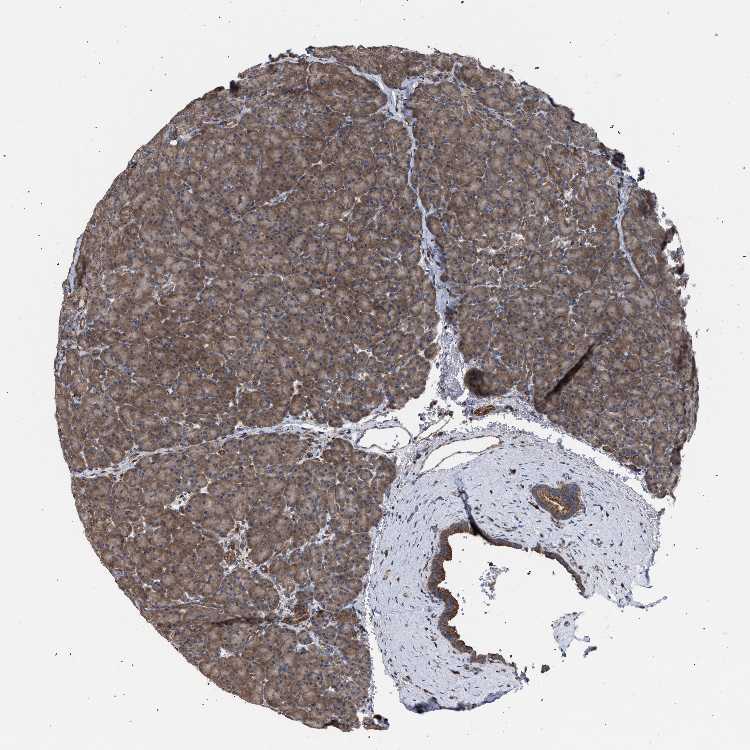

PANCREAS - Antibody stainingi

Antibody staining in the annotated cell types in the current human tissue is reported as not detected, low, medium, or high, based on conventional immunohistochemistry profiling in selected tissues. This score is based on the combination of the staining intensity and fraction of stained cells.

Each image is clickable and will lead to virtual microscopy that enables deeper exploration of all samples and also displays staining intensity scores, fraction scores and subcellular localization as well as patient and tissue information for each sample.

Antibody HPA022015

Exocrine glandular cells Medium

Pancreatic endocrine cells Medium